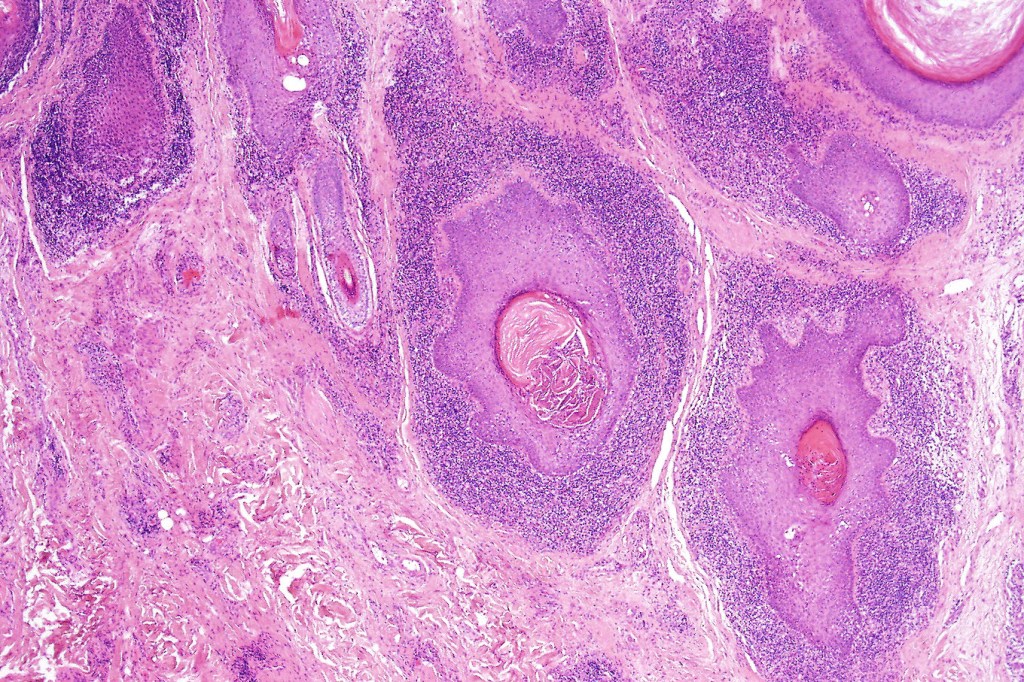

Histological features

•Epidermal involvement often absent

•Follicular infiltration by atypical lymphocytes & Sézary cells

•+/- mucinosis

•+/- syringotropic lesions

•+/- basaloid follicular hyperplasia

•Granulomatous inflammation secondary to follicular destruction